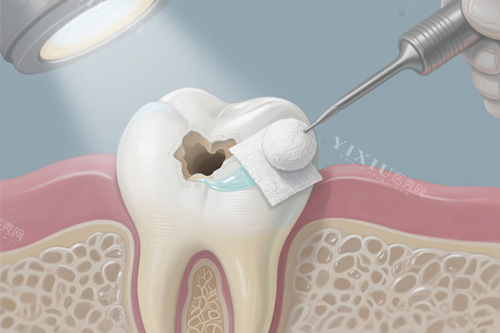

看技术:材料+设备,补牙更耐用

贝杰口腔补牙主打“精细操作+进口材料”。比如使用德国进口纳米树脂材料,硬度接近天然牙,且色泽可匹配20余种牙色,前牙修复后几乎看不出补过痕迹;配合口腔显微镜辅助,医生能更清晰观察龋坏边界,避免残留,降低二次龋坏概率。适合龋齿、楔状缺损、外伤导致的小面积牙体缺损人群。